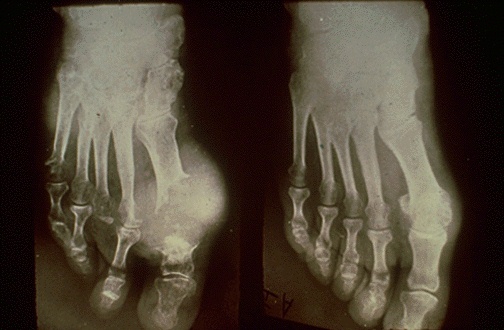

| Chronic gout leads to deposition of urates into a chalky mass known as a "tophus". Such tophi can destroy the joint and adjacent bone. The great toe is a common location for involvement. Seen here radiographically in sequential radiographs of the same foot (the patient did not have two right feet) is a tophaceous deposit that has destroyed the 1st MP joint and adjacent bone. In most, but not all, cases the patient has hyperuricemia. |